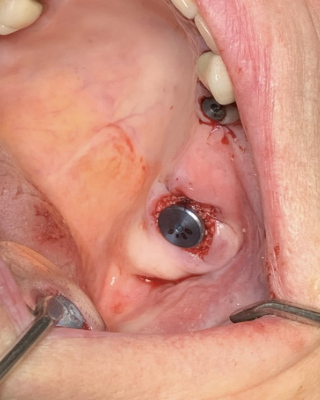

Patient se présente avec fracture de la 27 pilier de bridge.

Objectif : préservation osseuse alvéolaire résiduelle sur un site présentant une faible quantité d’os et le sinus en proximité immédiate.